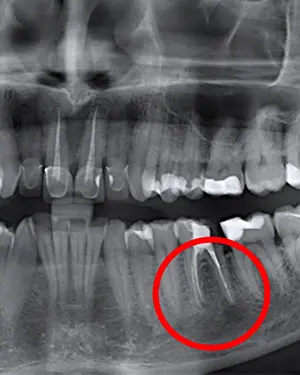

Ako osjećate bol ili oticanje zuba koji je već endodontski liječen, potrebno je zatražiti pomoć stomatologa. Stomatolog će u tom slučaju učiniti RTG snimku tog područja (zuba i okolne kosti) i klinički pregled kako bi se odlučilo je li potrebno napraviti apikotomiju. Korijenski kanali su vrlo složeni, naročito oko vrha korijena. Ponekad nakon endodontskog zahvata zaostane infektivnog debrisa unutar ogranaka kanala. To može dovesti do kasnije reinfekcije i potrebe za apikotomijom. Kod apikotomije se uklanja vrh korijena s upalnim i inficiranim tkivom i punjenjem kanala zapečaćuje se vrh korijena.